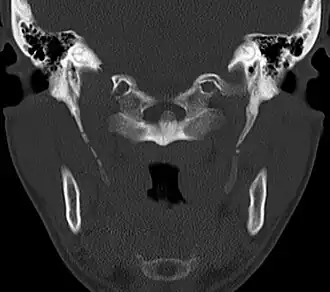

Imaging is important and is diagnostic. Visualizing the styloid process on a CT scan with 3D reconstruction is the suggested imaging technique.[13] The enlarged styloid may be visible on an orthopantogram or a lateral soft tissue X ray of the neck.